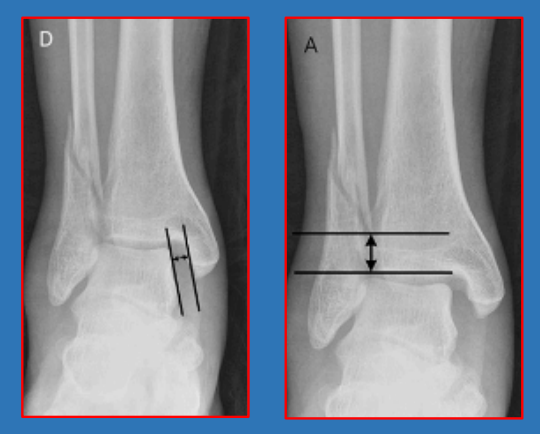

三角韧带损伤

内踝间隙medial clear space如果在前后位或踝穴位X线片上测得内踝与距骨的间隙(medialclear space)大于4mm,无论X线片是否是在应力下拍摄,都表示有三角韧带的损伤

下胫腓联合分离

胫腓间隙、重叠,胫腓间隙在前后位上大于6mm或胫腓重叠在前后位上小于6mm、在踝穴位上小于1mm,即表示存在下胫腓联合的分离。

踝穴宽度 D线在距骨关节面下方5mm处,平 行于距骨关节面,与胫骨、腓骨相 交于a、b、c、d四个点 、踝穴宽度=ab-cd 、正常范围2~6mm。

在旋后外旋SER类型中:内踝间隙>4.5mm、骨折高度>7mm